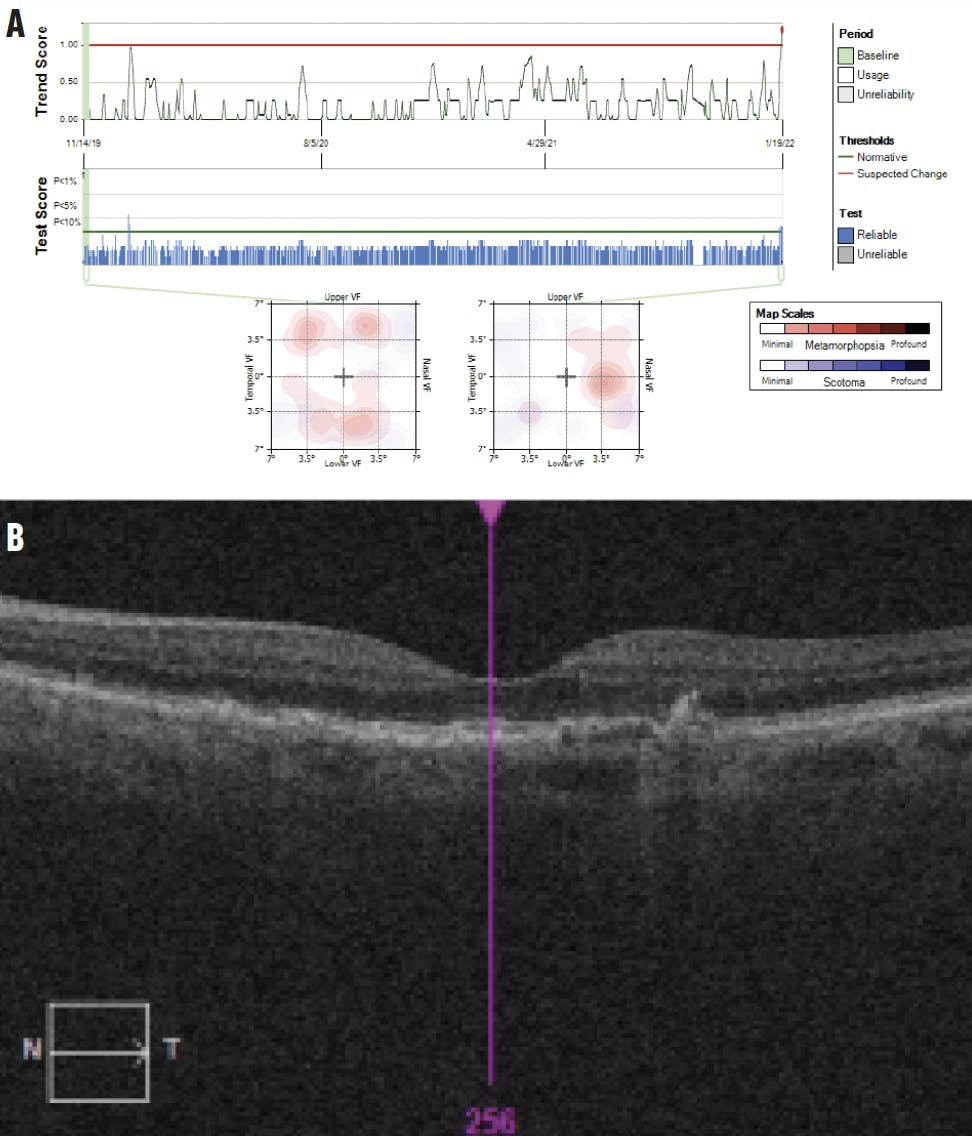

In January 2022, my office was alerted to aberrations in her at-home testing of the left eye. The patient presented the next day, explaining that her vision had not subjectively changed since last month’s visit. Dilated fundus examination did not show significant new abnormalities, but in-office OCT revealed a new, small CNV with very subtle subretinal fluid (Figure 7). Vision had dropped to 20/30 OS. She was diagnosed with conversion to wet AMD with active CNV in the left eye and received an intravitreal injection of an anti-VEGF agent.

<p>Figure 7. Six months after the right eye converted to wet AMD, at-home monitoring caught changes in the left eye (A), prompting in-office examination and a new diagnosis of wet AMD in the left eye (B).</p>

Figure 7. Six months after the right eye converted to wet AMD, at-home monitoring caught changes in the left eye (A), prompting in-office examination and a new diagnosis of wet AMD in the left eye (B).